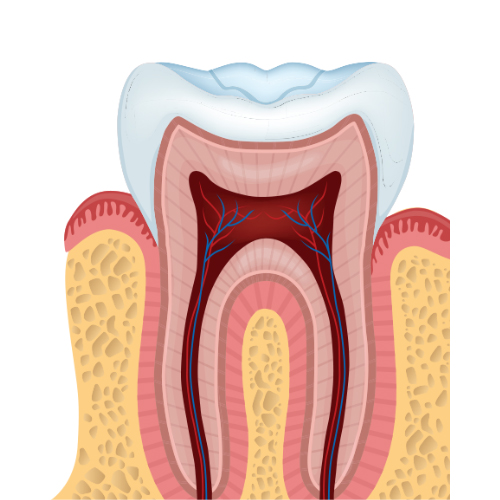

¿Qué es la sensibilidad dental?

Es el dolor o molestia que se produce debido a un desgaste de la superficie dental o retracción del tejido gingival.

Hipersensibilidad de la dentina: ¿por qué afecta a algunas personas y a otras no?

Descubra por qué algunas personas tienen una mayor probabilidad que otras de sufrir de hipersensibilidad de la dentina y cómo las y los estudiantes de odontología pueden reconocerla, diagnosticarla y tratarla.

La importancia de la prevención y el control de la hipersensibilidad de la dentina en pacientes con periodontitis

Manejar y prevenir el dolor causado por la hipersensibilidad de la dentina en pacientes con periodontitis es de suma importancia, y algunas de las soluciones son muy simples.

Conocimientos 1er año: Morfología y anatomía dental